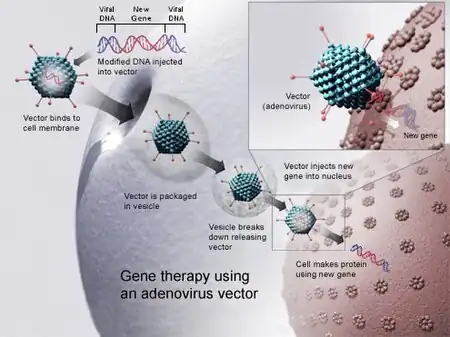

Gene therapy

Adenoviruses have long been a popular viral vector for gene therapy due to their ability to affect both replicating and non-replicating cells, accommodate large transgenes, and code for proteins without integrating genetic material into the host cell genome.[44] More specifically, they are used as a vehicle to administer targeted therapy,[84] in the form of recombinant DNA or protein. This therapy has been found especially useful in treating monogenic disease (e.g. cystic fibrosis, X-linked SCID, alpha1-antitrypsin deficiency) and cancer.[44] In China, oncolytic adenovirus is an approved cancer treatment.[85] Specific modifications on fiber proteins are used to target Adenovirus to certain cell types;[86] a major effort is made to limit hepatotoxicity and prevent multiple organ failure. Adenovirus dodecahedron can qualify as a potent delivery platform for foreign antigens to human myeloid dendritic cells (MDC), and that it is efficiently presented by MDC to M1-specific CD8+ T lymphocytes.[87]

A safety issue with adenoviruses is that they can cause an immue response with a related inflammatory respose as occurred in the death Jesse Gelsinger in 1999. To address this risk, the genome of the viral genes have been modified to remove some viral genes such. One such modification is the gutless vector that removes almost all the viral genome.[88]: 58

Adenovirus has been used for delivery of CRISPR/Cas9 gene editing systems, but high immune reactivity to viral infection has posed challenges in use for patients.[89]